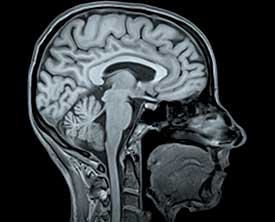

- КТ (компьютерная томография) головного мозга — первое исследование при подозрении на черепно-мозговую травму. Оно позволяет исключить внутримозговую гематому и выявить очаг ишемии, хотя последний может появиться только через 10-12 часов.

- В некоторых случаях назначают КТ или МРТ-ангиографию мозговых сосудов.

- МРТ